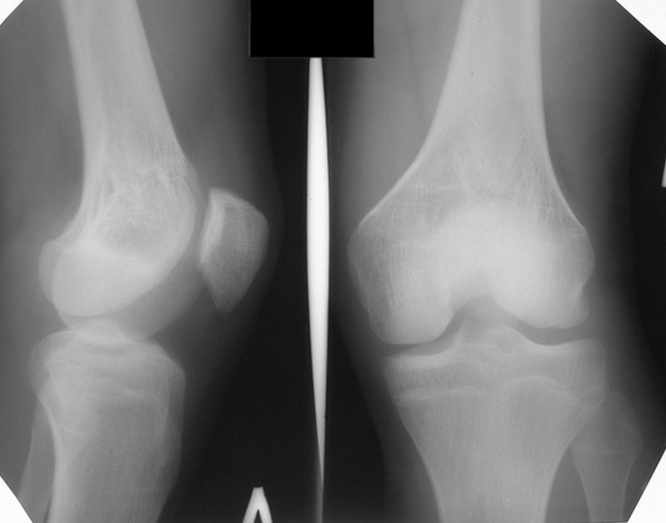

Из анамнеза: огнестрельное сквозное пулевое ранение бедра 9 лет назад в н/3 левого бедра. Раны зажили без гнойных осложнений. Жалобы на укорочение левой нижней конечности и нестабильность в коленном суставе. При обследовании выявляется рекурвация коленного сустава. Абсолютное укорочение порядка 5см, стоя 8 см (за счет рекурвации). Имеется умеренный компенсаторный сколиоз. С передне-наружной стороны располагается рубец от входного отверстия, с задне-медиальной стороны от выходного. Можно предположить повреждение при травме зоны роста бедренной кости и задне-внутренних стабилизирующих структур коленного сустава.

Trauma 9 ears ago: gunshot wound with bullet of the left knee. It Is Reeked have healed without festering complications. The patient have shorter femur and recurvatum instability of knee joint. Absolute shortening is 5 cm, at standing up 8 cm (genu recurvatum). The input scar is situated on the antero-lateral side and output scar is on the postero-medial side. It is possible to expect damage by trauma of the growing zone of the femur and back-internal stabilizing structures of the knee joint. We discuss the treatment options: to begin with lengthening of the femur or preferably with stabilizations of the knee joint. What is the optimal level to produce the lengthening of the femur in this case.